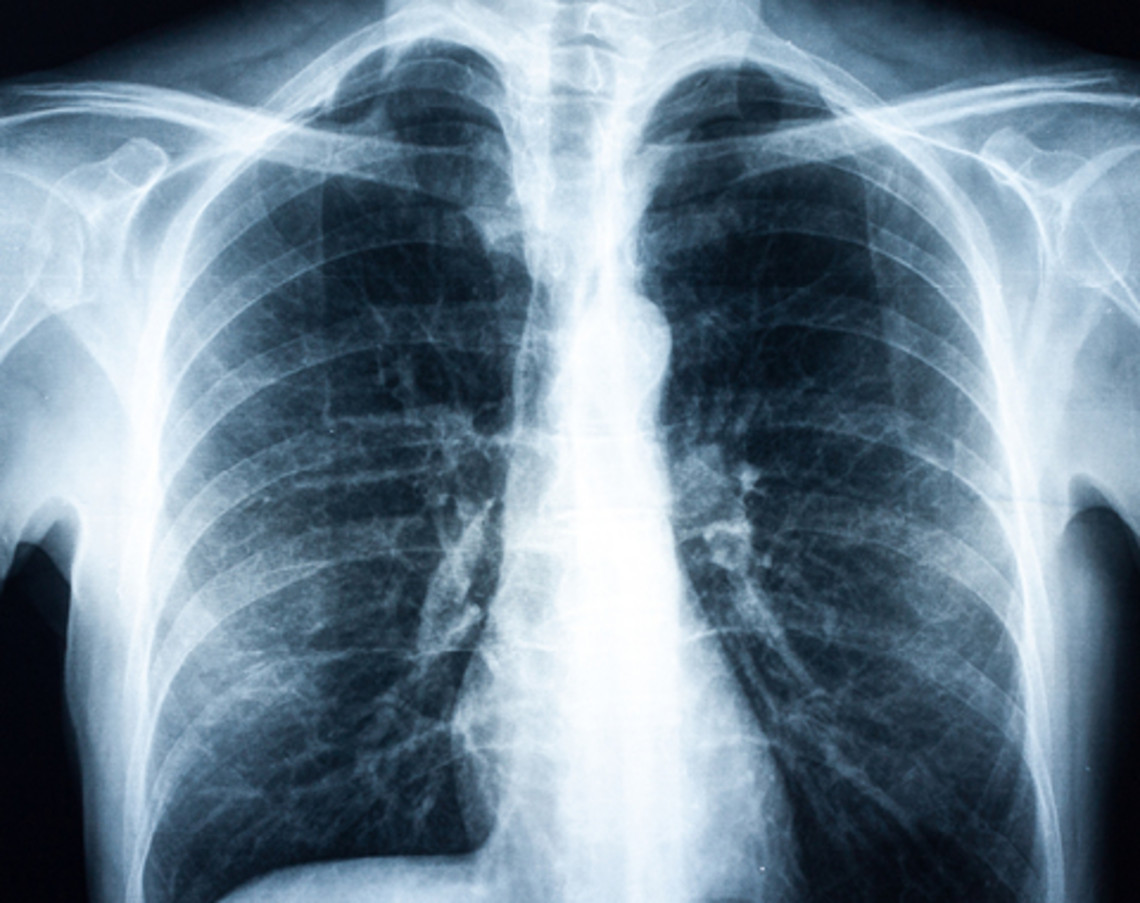

COPD usually progresses according to the following pattern: Chronic bronchitis develops over the years to chronic obstructive bronchitis, e.g. because of the lasting effects of cigarette smoke. This results in a narrowing (obstruction) of the bronchial tubes, which leads to shortness of breath during physical exertion. In advanced stages the alveoli are damaged (emphysema). Breathing out is more difficult and those affected often feel tired and exhausted.

Sometimes there can be a sudden deterioration in the disease (exacerbation). Those affected cough more violently, have more sputum, are more breathless and often have fever. It is often triggered by viral or bacterial infections of the airways or increased contact with harmful substances, but also by other diseas-es affecting the heart and lungs (e.g. pneumonia).